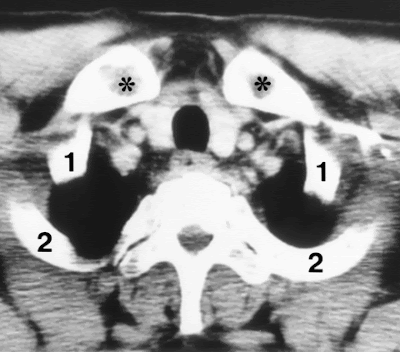

Rib counting at CT with the clavicle as an anatomic landmark. Axial CT scan shows the medial third of the clavicle (*) and the relative position of the first two ribs (1, 2).

Identifying the first rib in relation to the clavicles is easy and precise; however, counting ribs from the clavicles is tedious for middle and lower rib lesions. Furthermore, counting thoracic vertebrae may be imprecise owing to partial volume effect.